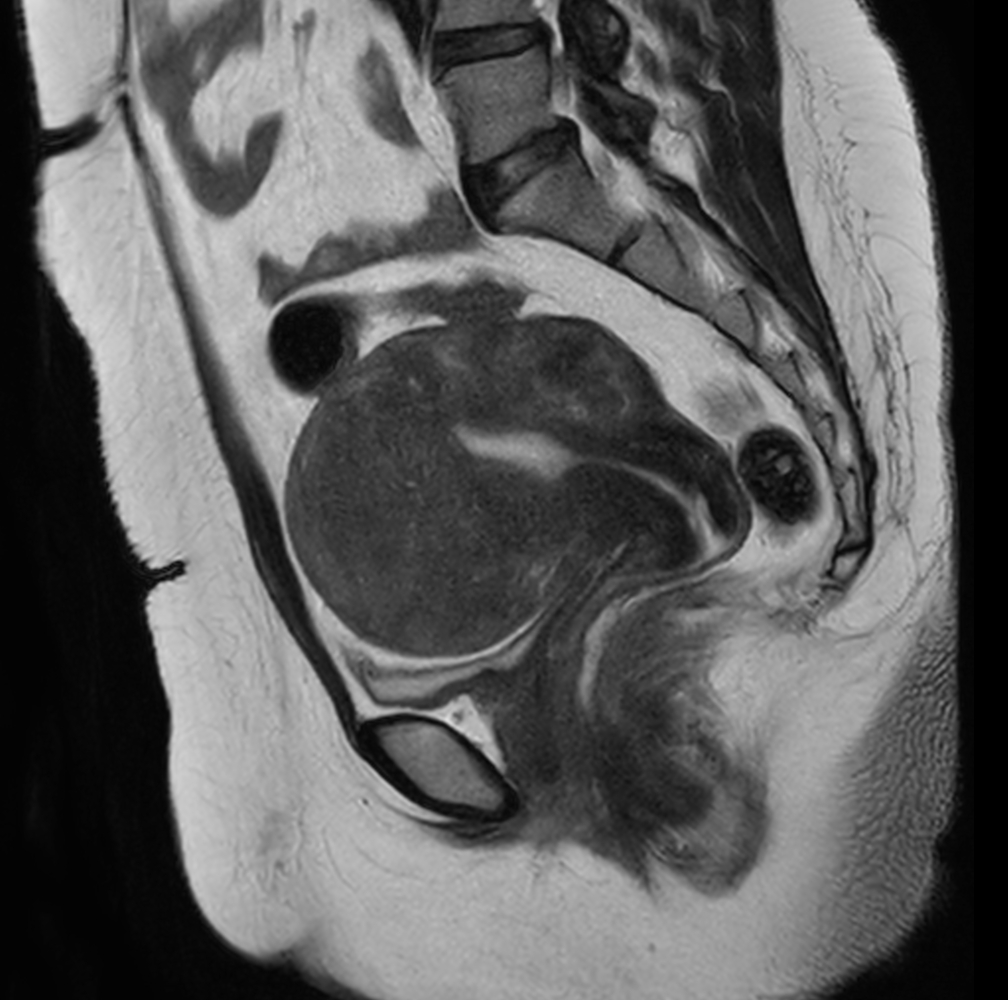

Sagittal T2w SSh